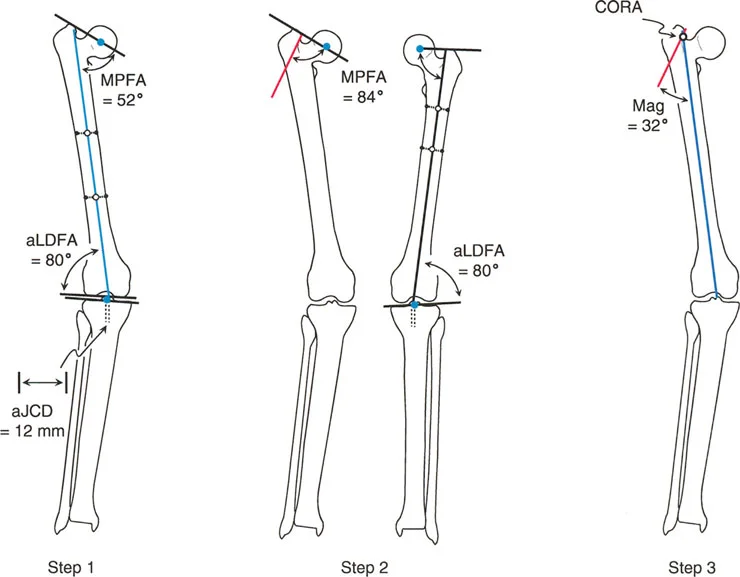

The Center of Rotation of Angulation (CORA) represents the apex of the deformity. To find the CORA, the surgeon draws the Proximal Mechanical Axis (PMA) line and the Distal Mechanical Axis (DMA) line.

* The PMA is drawn by taking the normal joint orientation angle from the proximal joint and extending a line down the shaft.

* The DMA is drawn by taking the normal joint orientation angle from the distal joint and extending a line up the shaft.

* The exact point where the PMA and DMA intersect is the CORA.

A bone may have a single CORA (unapical deformity) or multiple CORAs (multi-apical deformity). Identifying the precise location of the CORA is the prerequisite for determining where to cut the bone and how to hinge the correction.

Axis of Correction of Angulation

While the CORA is a fixed geometric point dictated by the patient's pathology, the Axis of Correction of Angulation (ACA) is the actual hinge point around which the bone segments are rotated during surgery.

The placement of the ACA is entirely under the surgeon's control. It can be placed on the convex cortex, the concave cortex, or even outside the bone entirely (as seen with external fixator hinges). The spatial relationship between the ACA and the CORA dictates the final alignment of the limb, the presence of translation, and changes in limb length.

Executing the Preoperative Plan

- Perform the Malalignment Test Draw the mechanical axis from the center of the femoral head to the center of the ankle. Measure the MAD. Determine if the mechanical axis falls in the medial, lateral, or central zone of the knee.

- Perform the Malorientation Test Draw the individual mechanical axes of the femur and tibia. Measure the mLDFA, MPTA, LPFA, and mLDTA. Compare these to normal values to isolate the source bone of the deformity.

- Locate the CORA Draw the Proximal Mechanical Axis (PMA) and Distal Mechanical Axis (DMA) using the normal joint orientation angles. Mark their intersection as the CORA.

- Select the Osteotomy Rule Determine if the bone can be safely cut at the CORA (Rule 1) or if the cut must be moved to the metaphysis (Rule 2).

- Choose the Osteotomy Sequence Decide between an opening wedge, closing wedge, or dome based on limb length discrepancy and soft tissue constraints.

- Simulate the Correction Using digital templating software, digitally cut the bone, place the ACA, and rotate the segment. Verify that the final mechanical axis passes through the center of the knee and that joint lines are parallel to the floor.